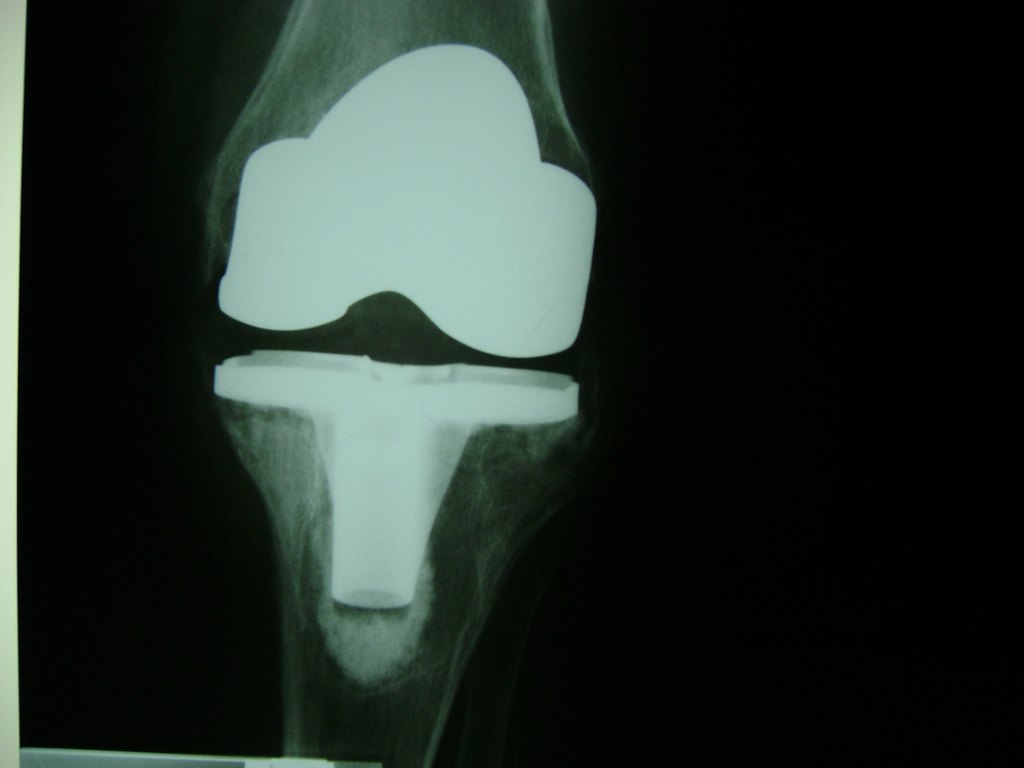

Cirugías de Rodillas

La artroscopia de rodilla es un cirugía en el cual la estructura interna de la articulación es examinada ya sea para realizar un diagnostico o para realizar un tratamiento, este procedimiento se realiza utilizando un instrumento parecido a un pequeño tubo llamado artroscopio.